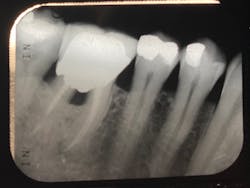

There are a multitude of reasons why patients may not respond properly to periodontal therapy or why their gums still bleed after a dental cleaning (figure 1).1 Of tantamount importance is to discern why previous therapy has not worked prior to reinitiating treatment or simply “giving the patient another cleaning.”

Studies have shown that multiple episodes of scaling and root planing (a deep cleaning) are no more effective than administering a single episode of scaling and root planing performed properly.1 The purpose of this article is to briefly discuss the top five reasons gingival inflammation persists after a dental cleaning.